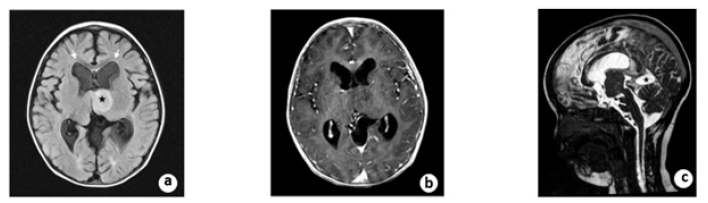

During the 16 months follow-up, the boy improved remarkably with a recovery of normal neurological status and psychomotor development. Post-operative MRI revealed contraction of the enlarged ventricles, shrinkage of the arachnoid cyst, and diminishment of periventricular edema. On the sagittal view of the 3D FIESTA, the floor of the third ventricle was elevated and vacant locally. The arachnoid cyst superior to the cerebellum shrank, and the compression of the aqueduct was relieved (Figure 5). The child is scheduled for annual follow-up currently.

Figure 5: A. Post-operative MRI scanning showed an intensive FLAIR signal (black star) and the diminishment of paraventricular edema (white arrow). B. The tumor was still not enhanced after contrast administration at follow-up. C. On the sagittal view of 3D FIESTA, the floor of the third ventricle was elevated and vacant locally. The arachnoid cyst (black star) superior to the cerebellum shrinks and the compression of aqueduct relieved.